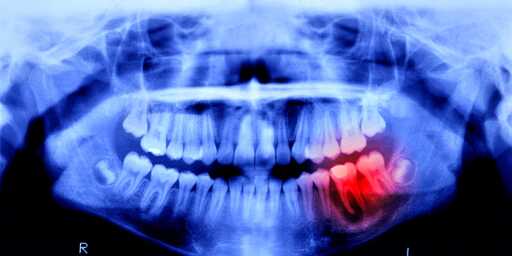

Now, scientists will see just how similar, because humans are undergoing a similar trial. Lasting 11 months, this study focuses on 30 males between the ages of 30 and 64—each missing at least one tooth. The drug will be administered intravenously to prove its effectiveness and safety, and luckily, no side effects have been reported in previous animal studies.

I’ve seen one of these talked about before, and the mechanism seemed to be in that one that there’s a gene in our DNA that triggers us to grow new teeth (that’s how we replace our baby teeth with adult teeth), but that that gene turns off after we grow in our set of adult teeth. It’s apparently the same gene that allows sharks to grow new teeth. What the drug does is it turns that gene back on, allowing us to grow new teeth to replace lost ones.

This might not be the same study though, as I’ve also seen one previously years ago that was about a drug that turned on a gene in our teeth to allow them to repair the enamel in them and fill in cavities by putting biodegradable gauze soaked in the drug inside a cavity and letting the tooth do the rest.